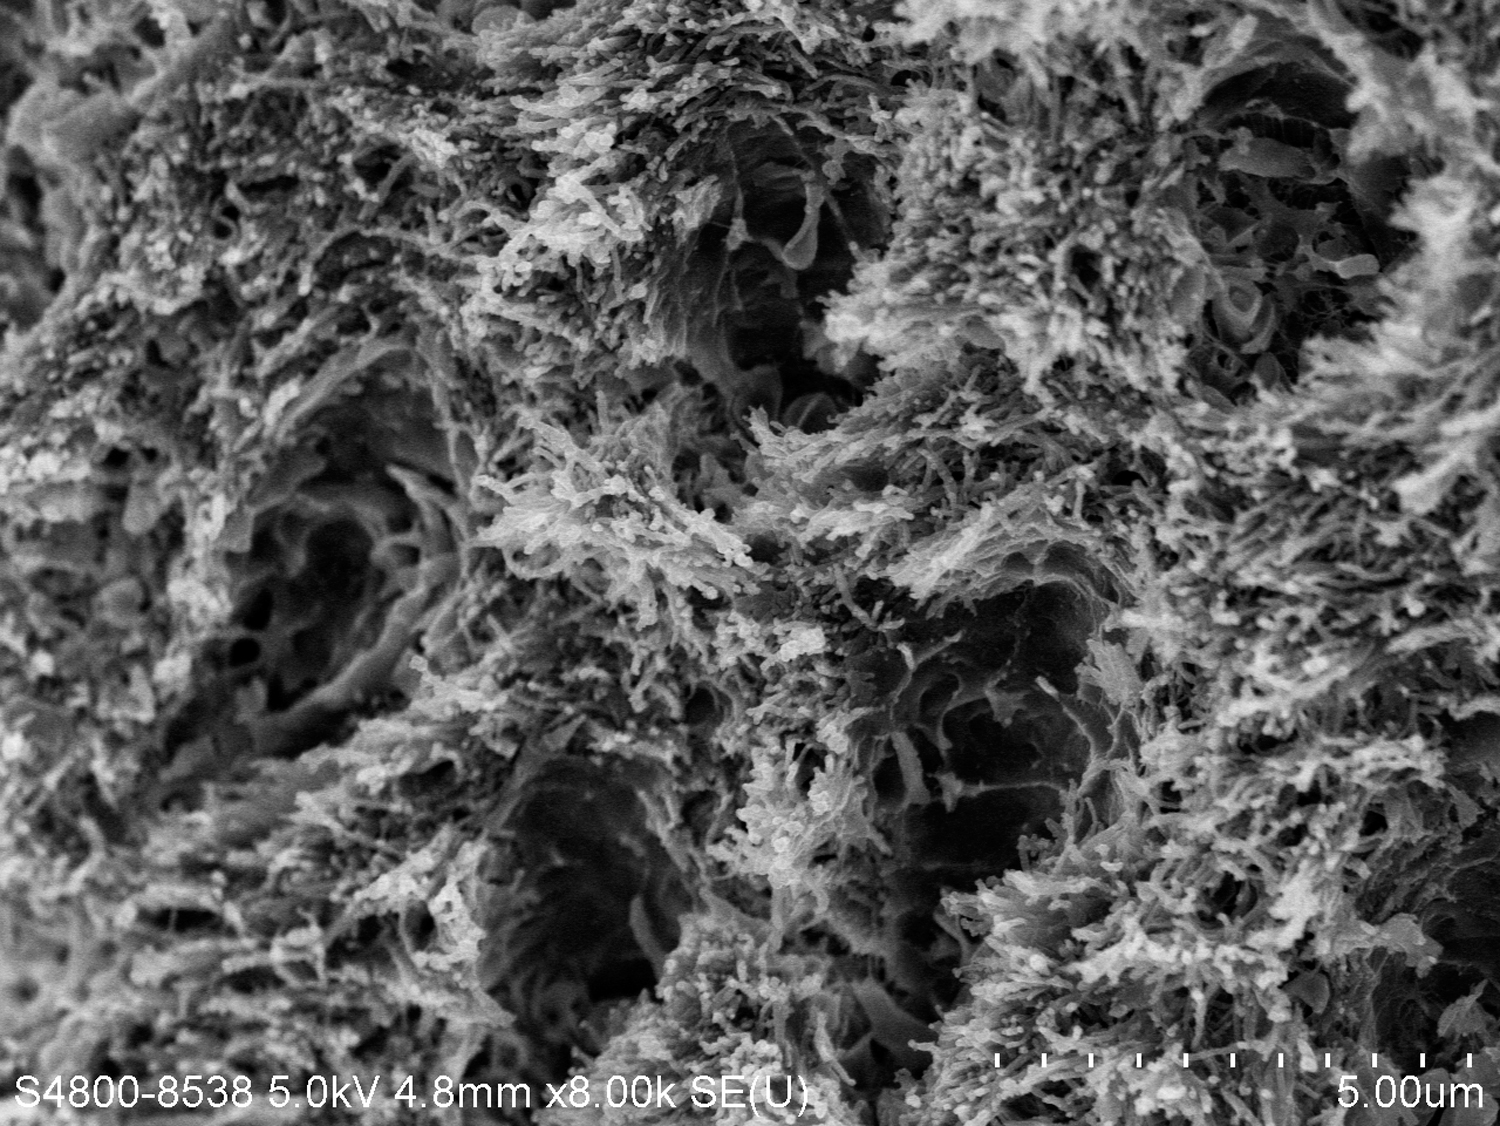

There are several advantages of using SDF in dental treatment. First, it showed an antimicrobial activity against mono-species, dual-species, and multi-species cariogenic biofilm.14-16 Silver ions are bactericidal metal cations that inhibit biofilm formation.17 Studies have indicated that silver interacts with sulfhydryl groups of proteins and DNA, thus altering hydrogen bonding and inhibiting respiratory processes, DNA unwinding, cell-wall synthesis, and cell division.18 At the macro level, these interactions affect bacterial killing and inhibit biofilm formation.17 Second, fluoride promotes caries lesion remineralization. Fluoride has been indicated to react with hydroxyapatite and generate calcium fluoride, which is a reservoir of fluoride, and facilitate further remineralization.19 An ex vivo study reported surface microhardness of the surface layer of the arrested caries after SDF applications was comparable with the unaffected sound dentin20 (Figure 1 and Figure 2). This is consistent with another study, in which a high remineralized zone was observed on the surface of arrested caries from exfoliated teeth with SDF treatment21 (Figure 3 and Figure 4). Third, its application procedures are simple and do not require injection or drilling, and the treatment does not involve expensive support infrastructure equipment such as piped water and electricity. The simplicity of the treatment is conducive to treating caries in apprehensive young children who may have intense dental fear, uncooperative patients with special needs, or elderly patients who have difficulty adapting to traditional dental care. It also allows trained workers to deliver the treatment to people who live in the area but who may not be able to easily access dental service.22 Patient compliance and satisfaction is often good when the patient is provided a clear explanation of the treatment outcome.23,24 Finally, the cost of SDF treatment is low and should be affordable in most communities.

Fig 3. Scanning electron microscope (SEM) images of the dentin carious lesions. Fig 3: Surface morphology of arrested carious lesion. Fig 4: Surface morphology of active carious lesion. (images from Mei, et al, 201421 [reprinted with approval])

Fig 4. Scanning electron microscope (SEM) images of the dentin carious lesions. Fig 3: Surface morphology of arrested carious lesion. Fig 4: Surface morphology of active carious lesion. (images from Mei, et al, 201421 [reprinted with approval])